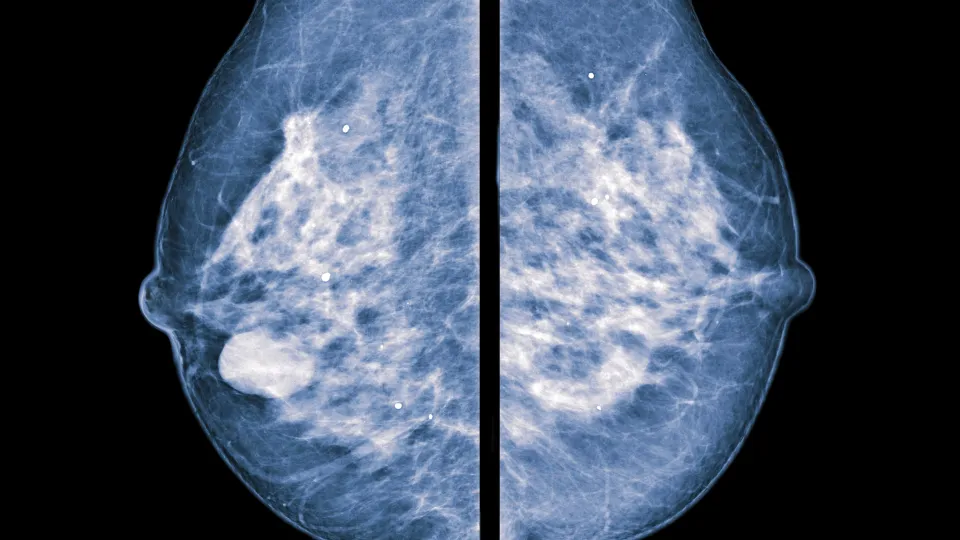

Precisionsmedicin gör det möjligt att ge patienter individanpassad vård utifrån tumörens egenskaper. Idag görs flera olika analyser av biomarkörer för att kartlägga dessa egenskaper – både kostsamma och tidskrävande. I takt med att användandet av detta växer, ökar även behovet av fler analyser. Det finns sekvenseringsteknologi tillgänglig inom sjukvården som kan analysera bröstcancerprov och kartlägga det som kallas multigensignaturer, alltså hur mycket RNA som uttrycks från olika gener vid ett givet tillfälle, i tumören. Nu visar forskare vid Lunds universitet att utifrån endast en enda RNA-sekvenseringsanalys kan man få många precisionsbaserade svar. Studien som har letts av cancer- och bioinformatikforskare vid Lunds universitet är publicerad i den vetenskapliga tidskriften npj Breast Cancer.